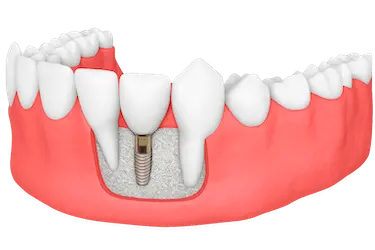

El injerto de hueso dental es una intervención quirúrgica rápida, segura y generalmente indolora, indicada cuando no existe suficiente hueso para colocar implantes dentales.

Con este implante de hueso dental conseguimos que nuestros pacientes tengan la calidad y, sobre todo, la superficie ósea necesaria para poder realizar el tratamiento.

Gracias al aumento de la cantidad de hueso, se consigue el espacio necesario para que los implantes se fijen de forma estable y con la inclinación adecuada, garantizando una prótesis segura y duradera.

El injerto de hueso maxilar es la mejor solución cuando el hueso del paciente es demasiado estrecho o demasiado corto para colocar un implante.

La regeneración ósea proporciona una buena sujeción, aumentando la anchura y la altura del hueso de manera que el implante dental pueda estar completamente anclado sin movimiento.